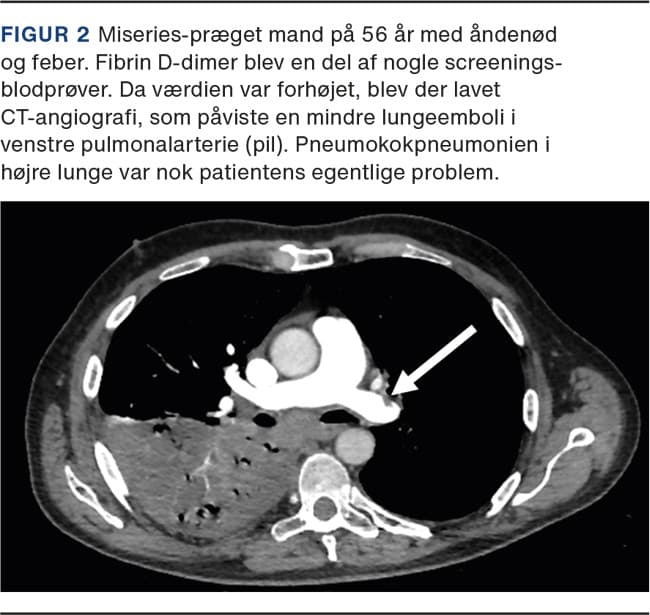

D-dimer er en akut fasereaktant og er forhøjet ved inflammationstilstande og infektioner [20]. En forhøjet D-dimer hos en inficeret, men ellers upåvirket patient kan derfor foranledige unødvendig udredning for lungeemboli. Man bør også huske, at forekomsten af incidentelle lungeembolier, som findes ved CT’er lavet på anden baggrund, er betydelig [21]. Da infektionssygdomme i sig selv disponerer til venøs trombose, skal man derfor have proportionerne i orden (Figur 2). Fund af lungeemboli uden klinisk betydning kan resultere i blodfortyndende behandling, uden det har påviselig effekt. Man kan sågar ende med anbefaling om livslang direkte oral antikoagulant i reduceret dosis, når der nu ikke var en oplagt årsag til lungeembolien [22]. Dette kan betyde, at patienten får øget blødningsrisiko på lang sigt grundet et tilfældigt fund [22].